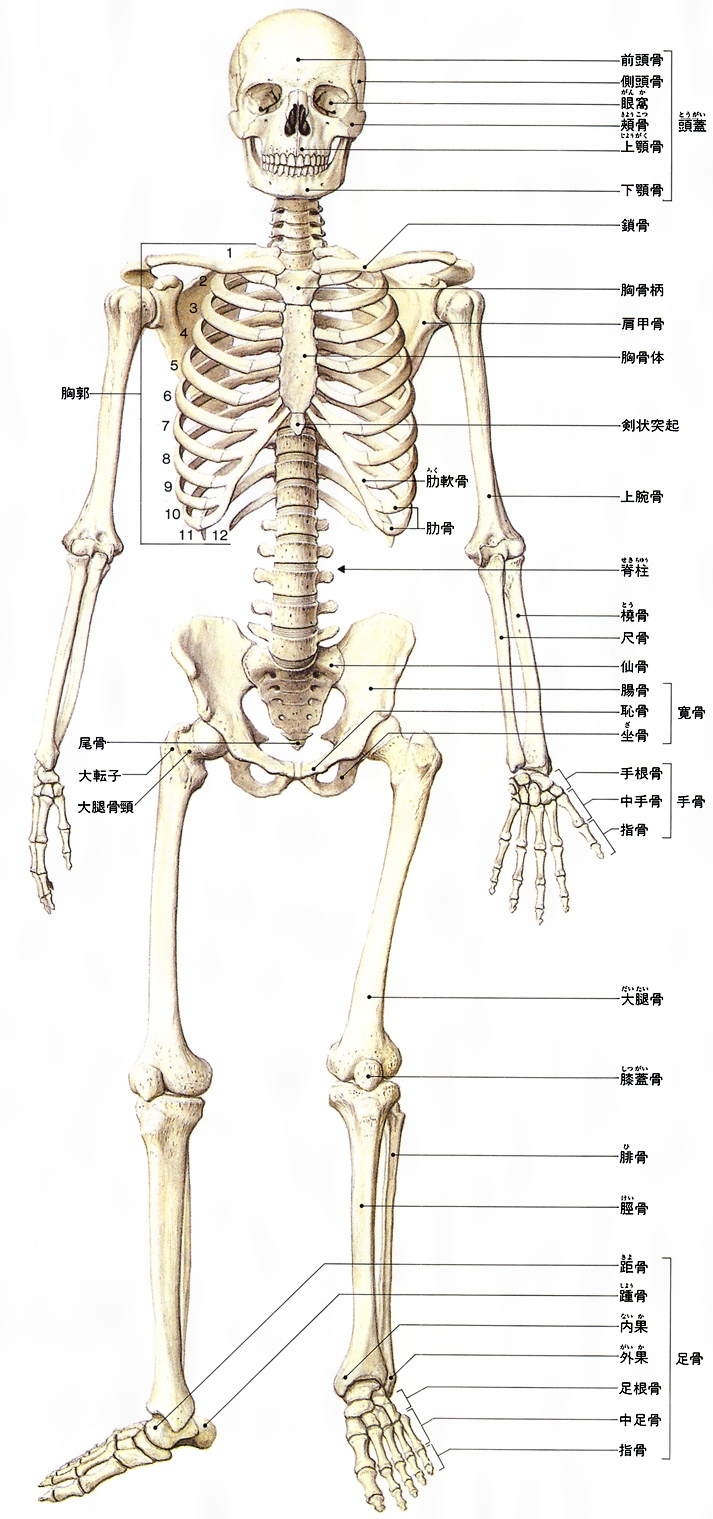

人間 骨 構造

人間 骨 構造. 人間の ほね 骨は、全部で何本あるの 生まれたばかりの赤ちゃんの骨の数は、約305個もあります。それが、成長し ていくにしたがって、はなれていた骨がくっついて一つになったり、いくつかの骨. 次は、関節の構造の解説です。 関節の構造 人間のカラダには約650の筋があり、 カラダを動かすことに使われる筋(骨格筋)は、 そのうちの約400です。 一部の例外を除いたすべての骨格筋は、 別々の骨と骨に「関節」を介してつながっています。 ですので、. 腱が骨や関節の近くを通過するところに存在し,腱の方向 を変える働きをする。 骨の組織構造7 緻密質にみられる骨の典型的な組織構造を,ハヴァース 系という。血管の通路であるハヴァース管Haversian canal を,厚さ数μmの骨層板bone lamellaが同心円状に取り巻.

骨構造 人体のあらゆる骨は、骨のあるプレート、クロスバー、そして梁で構成されています。 唯一の違いは、これらの要素のコンパクトさです。 管状の骨の部分では、外側の骨の物質は密で、内側の方がより砕けやすいです。 人間の下肢の骨格構造は. 階層構造 人体を要素に分解しながら見てゆくことも可能である。 骨は細かく分類すると0 人間は、意識的であれ無意識的であれ、人体をコミュニケーションの媒体としても用いている。. よくクイズで問題になることがありますが、人間の骨はいくつあるかご存知ですか? 答えは 成人は約6個 といわれています。 「約」と書いたのは、人によって欠けている骨もあるからです。.

骨 の最も基本的 人間の場合、成長とともに脊椎は弯曲(わんきょく)し始め、頚椎が前弯、胸椎が後弯、腰椎が前弯してs字状のカーブを描くようになります。 骨格筋の構造|動く(3).

コレクション骨名称